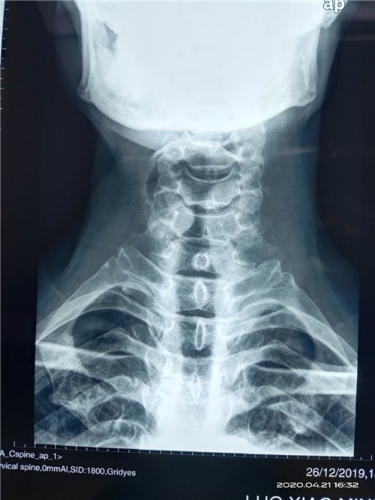

近日,昆明市延安医院呈贡医院(呈贡区人民医院、呈贡区中医医院)外一科为一位寰枢关节脱位患者成功实施了后入路颈1、2复位椎弓根螺钉内固定手术,患者术前诊断为:“寰枢关节脱位”。曾到过省内多家大医院就诊,因害怕手术风险,未敢做手术,后慕名前来我院,外一科主任杨旭民主任医师仔细查看患者及相关资料后收住院,并与患者及家属耐心讲解病情及手术方法、手术风险后,患者同意在我院手术,经过术前准备后于4月21日外一科在杨旭民主任带领下为患者成功实施了后入路颈1、2复位椎弓根螺钉内固定手术。术后患者寰枢关节脱位完全复位,固定满意。于4月22日由ICU安全转回普通病房。

术前图片如下:

微信图片_20200507143053